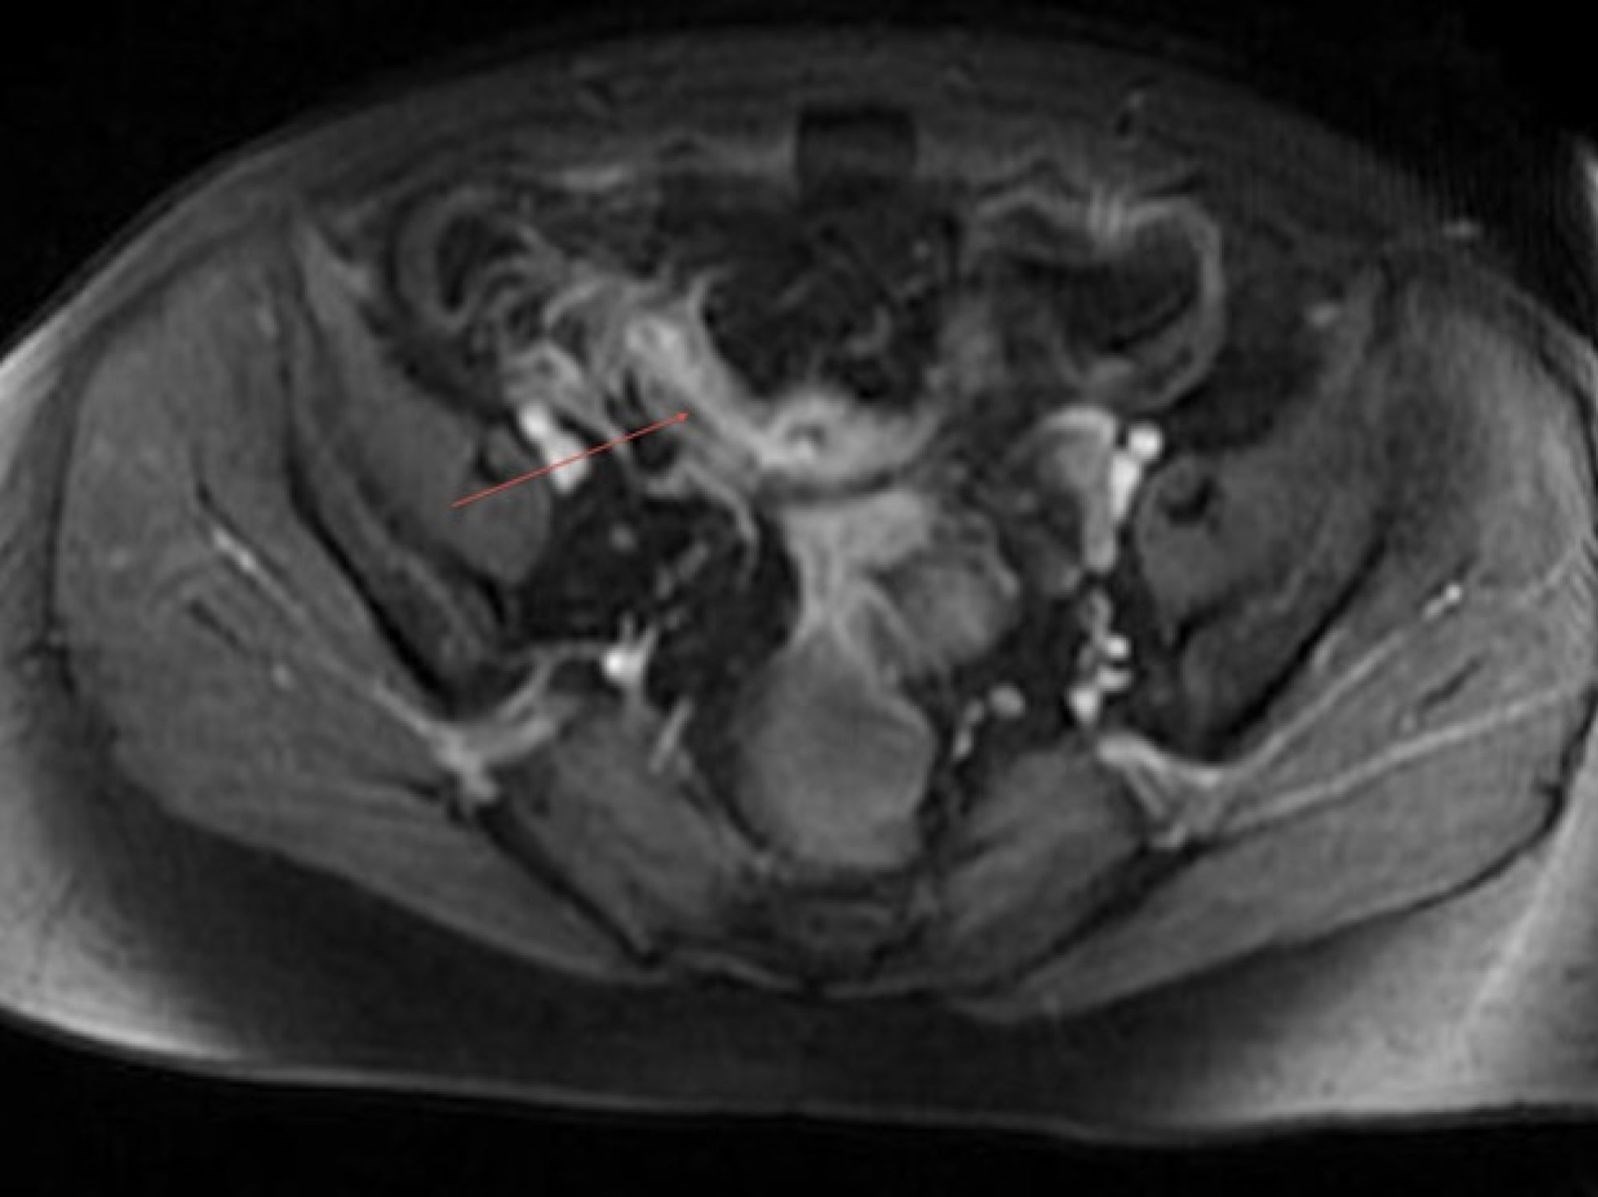

به گزارش خبر فوری به نقل از تسنیم، این زن 41 ساله تصور می‌کرد از بیماری کرون رنج می‌برد و پزشکان نیز تشخیص داده بودند که او مشکل روده دارد مورد عمل جراحی قرار گرفت و از روده او بقایای پاکت سُس مربوط به برند «هینز» خارج شد.

درد شدید بیمار در نهایت پزشکان را مجبور کرد که با جراحی سوراخی در شکم بیمار ایجاد کنند. سوراخی که در دیواره روده کوچک بیمار ایجاد شد اما پزشکان را با منظره عجیبی مواجه کرد.

در روده کوچک بیمار دو قطعه پلاستیکی مربوط به بسته‌بندی پلاستیکی یک سُس با نام تجاری معروف Heinz پیدا شد.

پزشکان در این رابطه گفتند که این قطعات بسته بندی پلاستیکی در بدن بیمار علائم بیماری کرون را تقلید می‌کرد و در تشخیص درست مشکل آنها را گمراه کرده بود.

با خارج شدن این قطعات پلاستیکی درد بیمار از بین رفت و در حال حاضر در حال سپری کردن دوران نقاهت خود است.